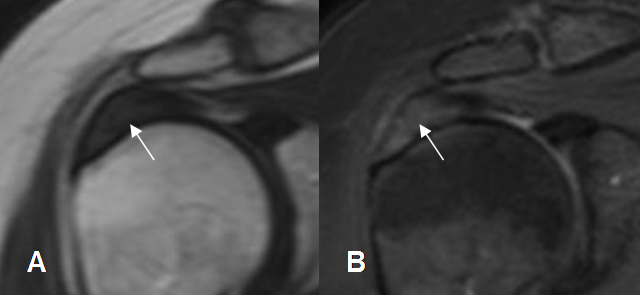

Fig 135. Tendinitis crónica del supraespinoso.

A: RM coronal en T1 y B: RM coronal en T2. Engrosamiento del tendón supraespinoso, el cual es hipointenso en ambas secuencias, por fibrosis secundaria a inflamación crónica. (Flechas gruesas). Además hay lesiones osteocondrales en la cabeza del húmero. (Flechas delgadas).